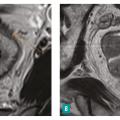

– la présence ou non d’arguments en faveur d’une histologie mucineuse, de plus mauvais pronostic (tumeur en hypersignal T2)4 [fig. 4 ] ;

– la présence ou non d’arguments en faveur d’une histologie mucineuse, de plus mauvais pronostic (tumeur en hypersignal T2)4 [